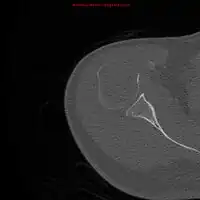

-

1.a. X-ray: solitary plasmacytoma upper arm near shoulder -

1.b. CT scan: solitary plasmacytoma upper arm near shoulder -